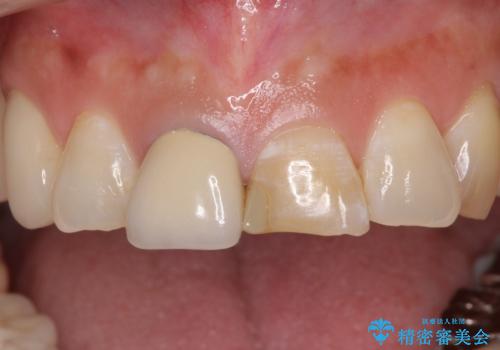

- 上の前歯2本が不調和であることを気にして来院された患者様です。

以前に前歯をぶつけた際、一方は神経を取り除いたためクラウンを装着し、もう一方は神経が残せたため一部修復をしていたとのことでした。

神経は残せていましたが、歯の色の変色が著しく、また広がった大きな形をしていたため、前歯2本をオールセラミッククラウンにて補綴することとしました。